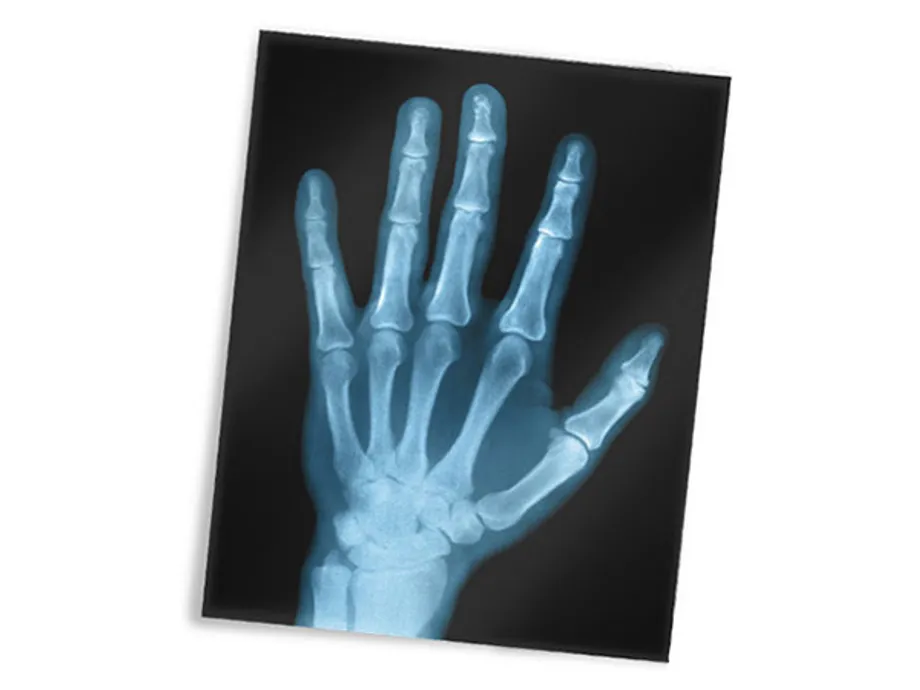

X-ray image of hand

This image, or radiograph, is a modern X-ray of a hand. One of the first X-ray photographs was made of the hand of Röntgen's wife.

The image displayed both her wedding ring and bones. A radiograph is an X-ray image obtained by placing a part of the patient in front of an X-ray detect or and then illuminating it with a short X-ray pulse.

Bones contain much calcium, which due to its relatively high atomic number absorbs X-rays efficiently. This reduces the amount of X-rays reaching the detector in the shadow of the bones, making them clearly visible on the radiograph.